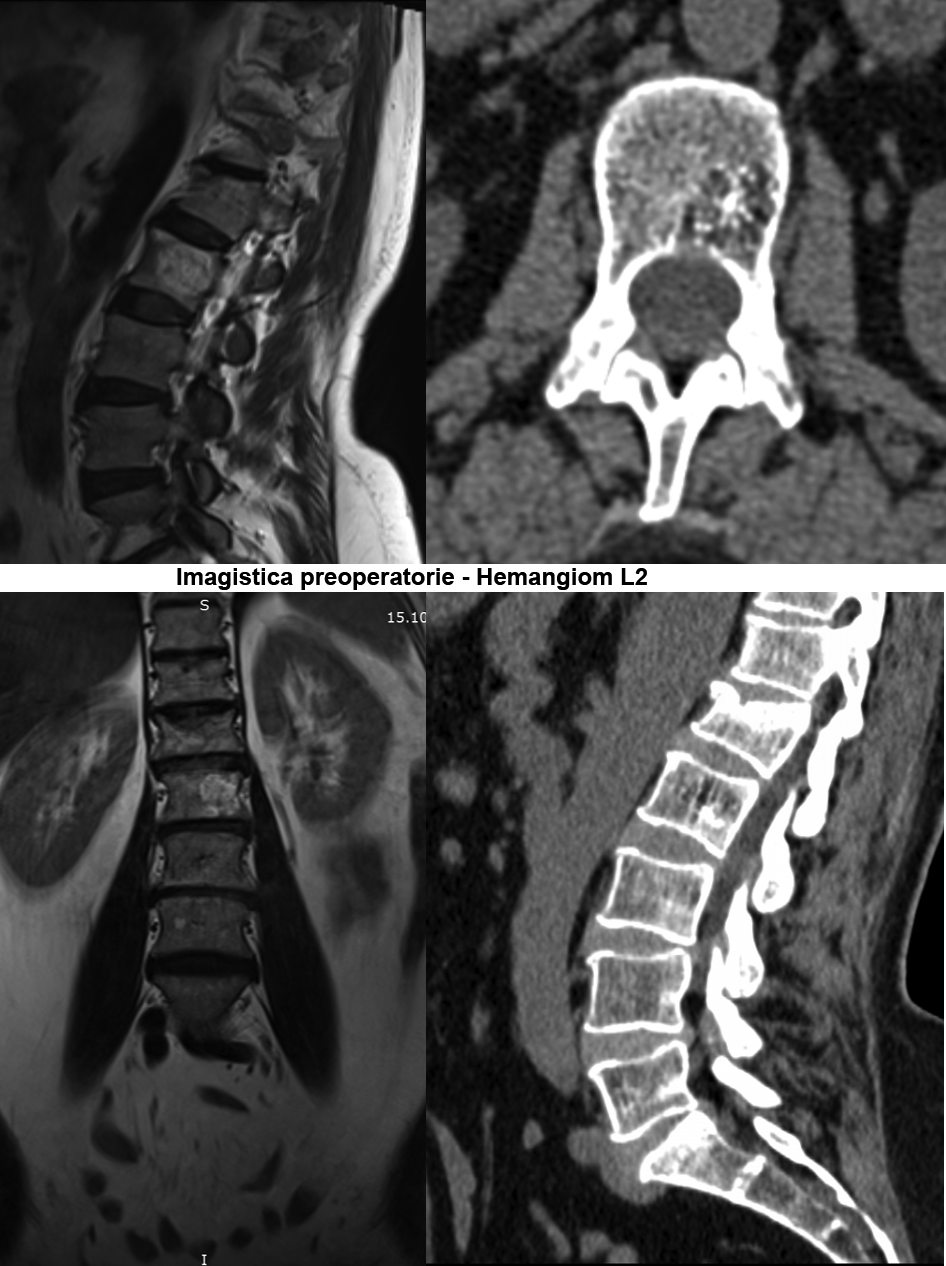

În urma investigaţiilor imagistice prin CT şi IRM a coloanei lombare, a fost stabilit diagnosticul Fractură tasată a corpului vertebral LI gr.II şi Hemangiom agresiv al hemicorpului vertebral LII pe stânga. Luând în considerare datele clinice şi paraclinice, s-a decis de a trata simultan aceste două vertebre, prin combinarea a două tehnici chirurgicale minim invazive – vertebroplastia percutanată şi kyfoplastia cu baloane expandabile.

Vertebroplastia percutanată (VTP) reprezintă injectarea unui ciment acrilic (metilmetacrilat) în vertebra patologic modificată sub control fluoroscopic sau tomografic. Această tehnică a fost propusă în 1984 de către neurochirurgul francez Pierre Galibert pentru tratamentul preoperator al unui hemangiom agresiv de vertebră cervicală, pentru a diminua hemoragia intraoperatorie. Ulterior, vertebroplastia a fost propusă pentru tratamentul fracturilor vertebrale osteoporotice şi în metastazele vertebrale cu sindrom algic pronunţat.

Majoritatea fracturilor vertebrale au loc în segmentul toracic inferior sau lombar superior şi sunt cauzate de traumatisme, osteoporoză sau tumori ale coloanei vertebrale. Scopul operaţiei este de a „întări” vertebra fracturată cu ciment special predestinat acestor scopuri. Vertebra în care a fost introdus cimentul devine mai rigidă, mai stabilă, iar în urma acestui fapt are loc diminuarea semnificativă a durerilor preoperatorii. Eficienţa tratamentului prin vertebroplastie şi kyfoplastie este de peste 90% în funcţie de tipul şi localizarea fracturii vertebrale. Acest tip de operaţii este unul sigur, poate fi aplicat pacienţilor în vîrstă, care suferă cel mai frecvent de osteoporoză, iar rata complicaţiilor se situează sub 1%.